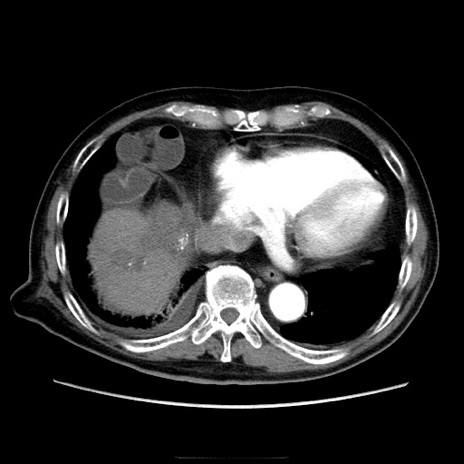

症例21(横断像)

【症例】70歳代男性

【主訴】腹痛

【現病歴】肝硬変・肝細胞癌にてかかりつけの方。約9時間前に食後より腹痛出現。症状が徐々に増悪し、嘔吐出現したため来院。

【既往歴】肝硬変、肝細胞癌(RFA、TACE後)

【身体所見】意識清明、表情苦悶様、BT 36℃、BP 129/78mmHg、P 88bpm、SpO2 97%(RA)、右上腹部から心窩部にかけて圧痛あり、反跳痛なし、筋性防御あり。

【データ】WBC 5800、CRP 0.16